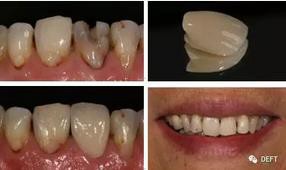

15.氧化鋯修復(fù)體的美學(xué)外觀有改良么?

在過(guò)去的三年,氧化鋯修復(fù)體的美觀程度大大提高。這項(xiàng)趨勢(shì)還將延續(xù),在以愛(ài)爾創(chuàng)“玉瓷”(透度高達(dá)49%)為代表的新型氧化鋯產(chǎn)品的不斷推出,相信最終會(huì)達(dá)到及超越烤瓷冠的外觀。(圖8)

360截圖20170125143722921.jpg

圖8  愛(ài)爾創(chuàng)-UPcera“玉瓷”全鋯冠前牙修復(fù)